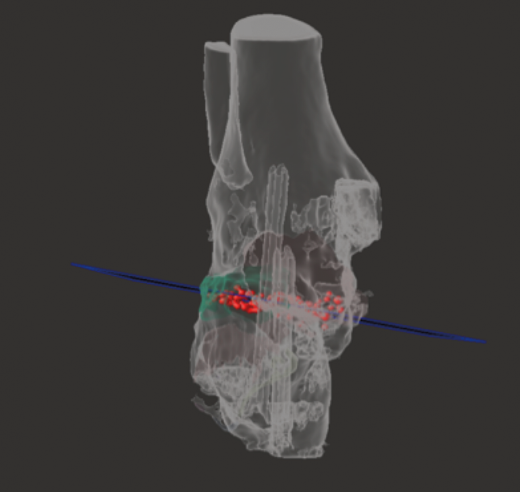

Utilidad de la impresión 3D: se decidió imprimir una guía 3D de corte como ayuda intraoperatoria. La guía permite la resección de la coalición de manera completa y reducir la necesidad de guía con fluoroscopia.

- Diseño de la guía de corte guiada por aguja de Kirschner (Figura 12).

- Colocación de la guía intraoperatoria sobre relieves óseos (Figura 13).

- Resección intraoperatoria (Figura 14).